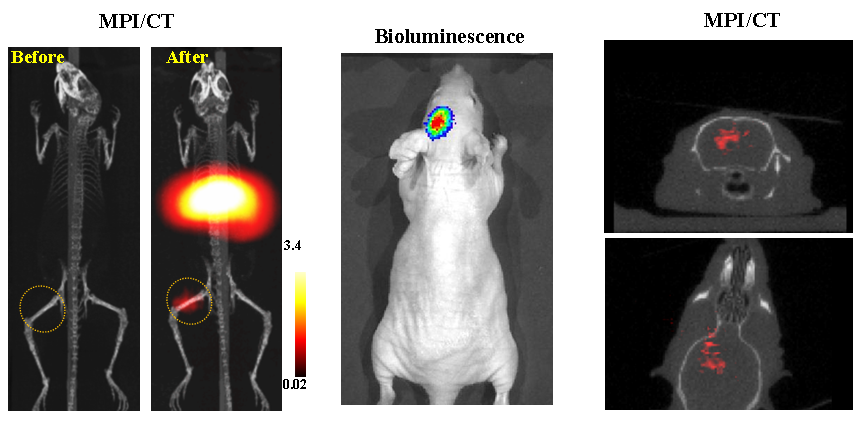

今年二月份,宋国胜教授与斯坦福大学饶江宏教授合作,通过系统的研究获得了影响磁性粒子成像信号的作用规律和关键原理,开发了新型磁性粒子探针---FeCo合金粒子,并首次应用于磁性粒子成像(MPI)。该造影剂在极低含量时(5 ng)仍具有很强的造影效果。这意味着,未来在进行人体成像时,可以使用更小剂量的造影剂,从而避免高剂量造影剂引起的肾肝损伤。基于MPI的直接成像原理,我们可以对造影剂进行正相和无背景干扰的活体成像,极大地提高信噪比。这项技术为肿瘤早期诊断、癌细胞示踪、脑中风、药物输送治疗、肺部灌注成像、胃肠出血、神经退行性疾病、磁热治疗等在活体中的可视化研究,提供了强有力的手段。相关研究成果以开云kaiyun官方网站为第一单位发表在Nature 子刊《Nature Biomedical Engineering》。该期刊是“生物医学工程”的顶级期刊。宋国胜教授为该论文的共同通讯作者。